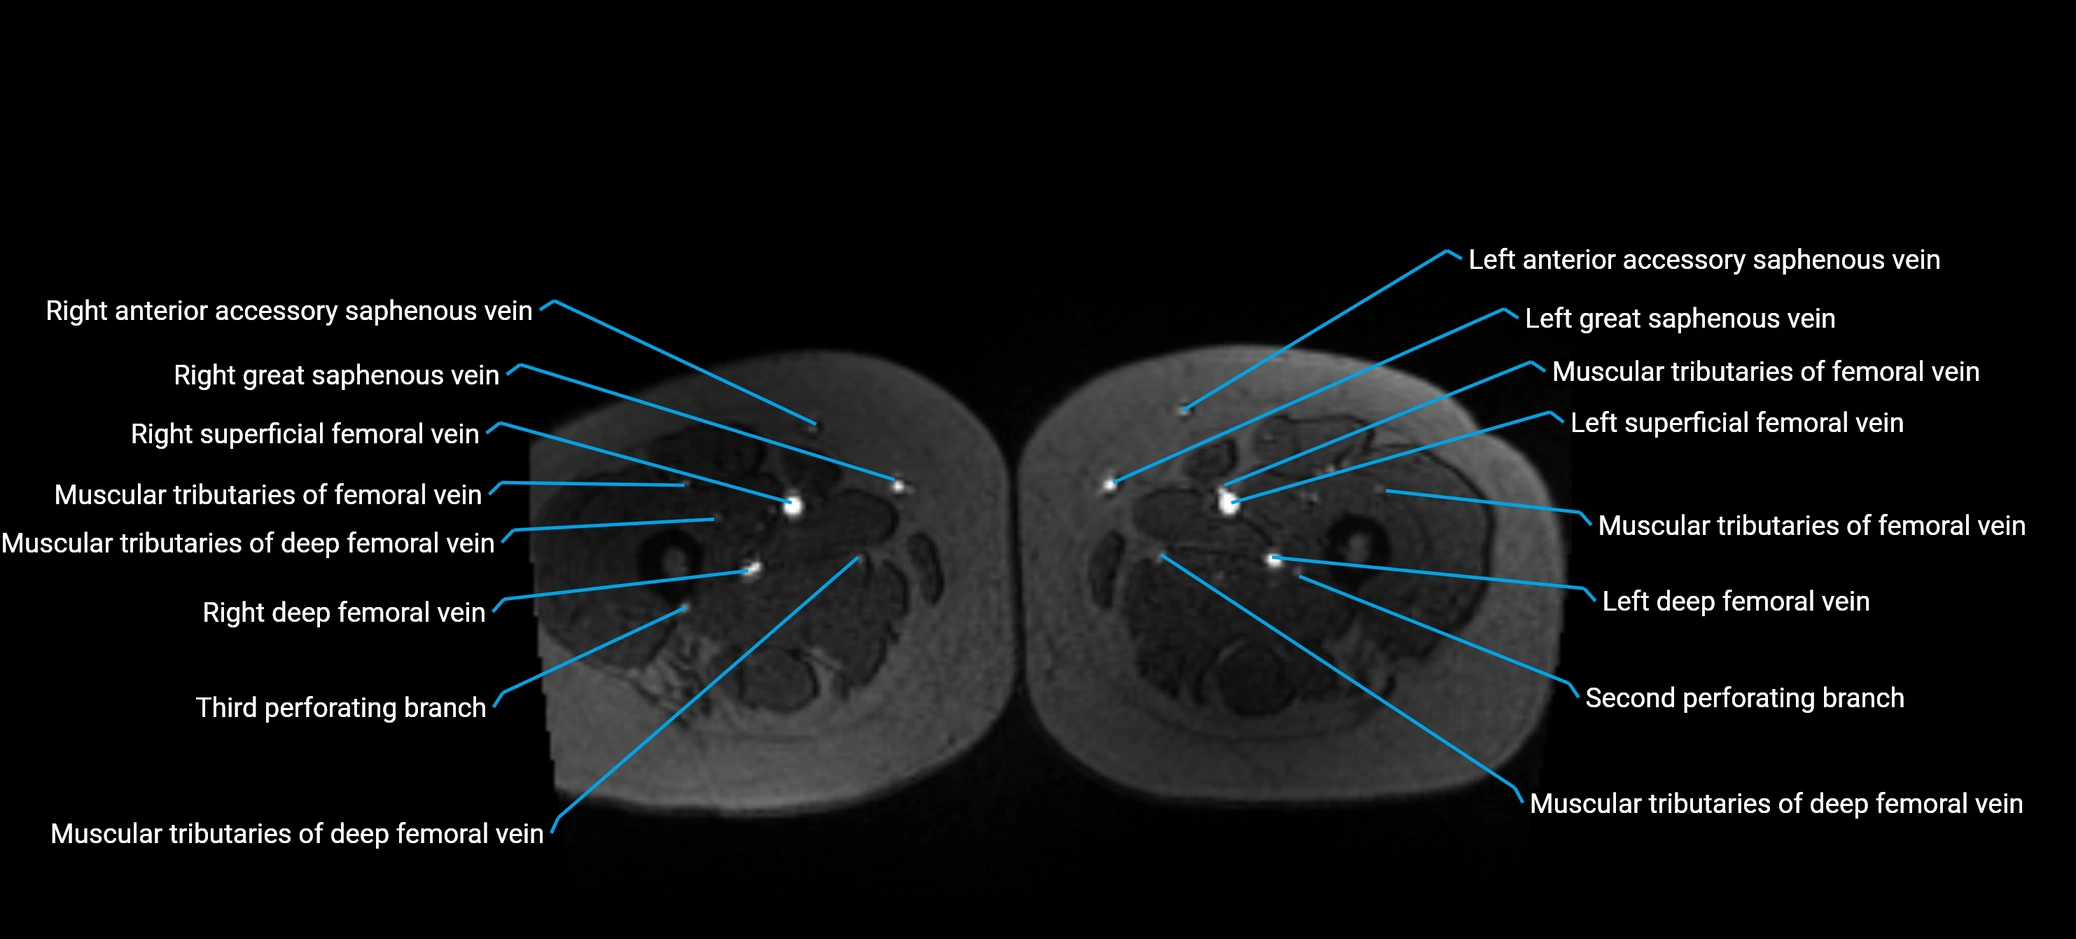

MRI image

image